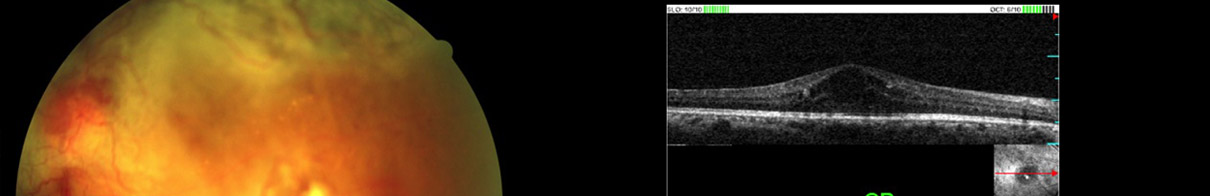

| Before Surgery |